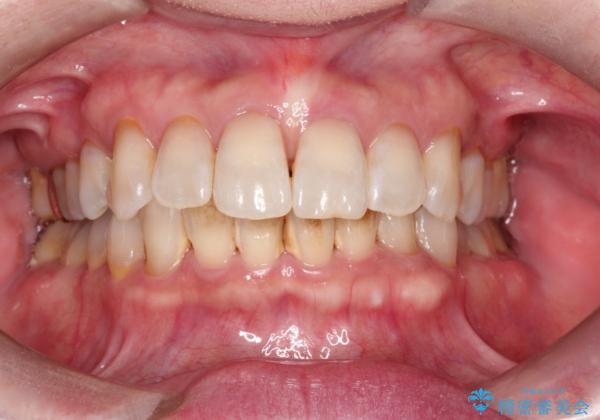

PMTCでステイン除去をし綺麗な歯へ

ステインを除去したことで全体のトーンが明るくなりました。下顎前歯は歯石で埋まってしまっていたため、クリーニング後はスペースができたように見えますが、歯本来の形へ戻りました。